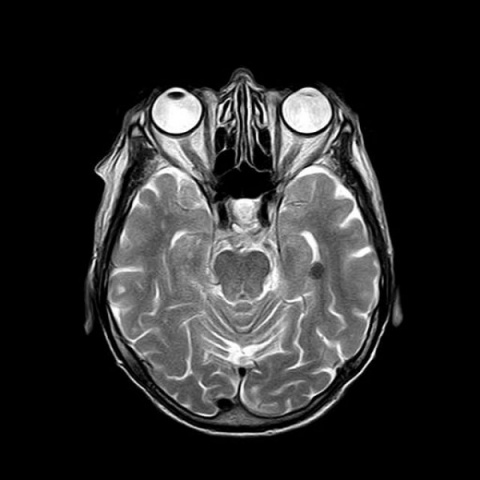

Imagen de microscopía del giro dentado del hipocampo. Los colores muestran la expresión de genes en algunos de los distintos estados celulares descritos en el estudio. (Foto: FIL / CONICET. CC BY 2.5 AR)